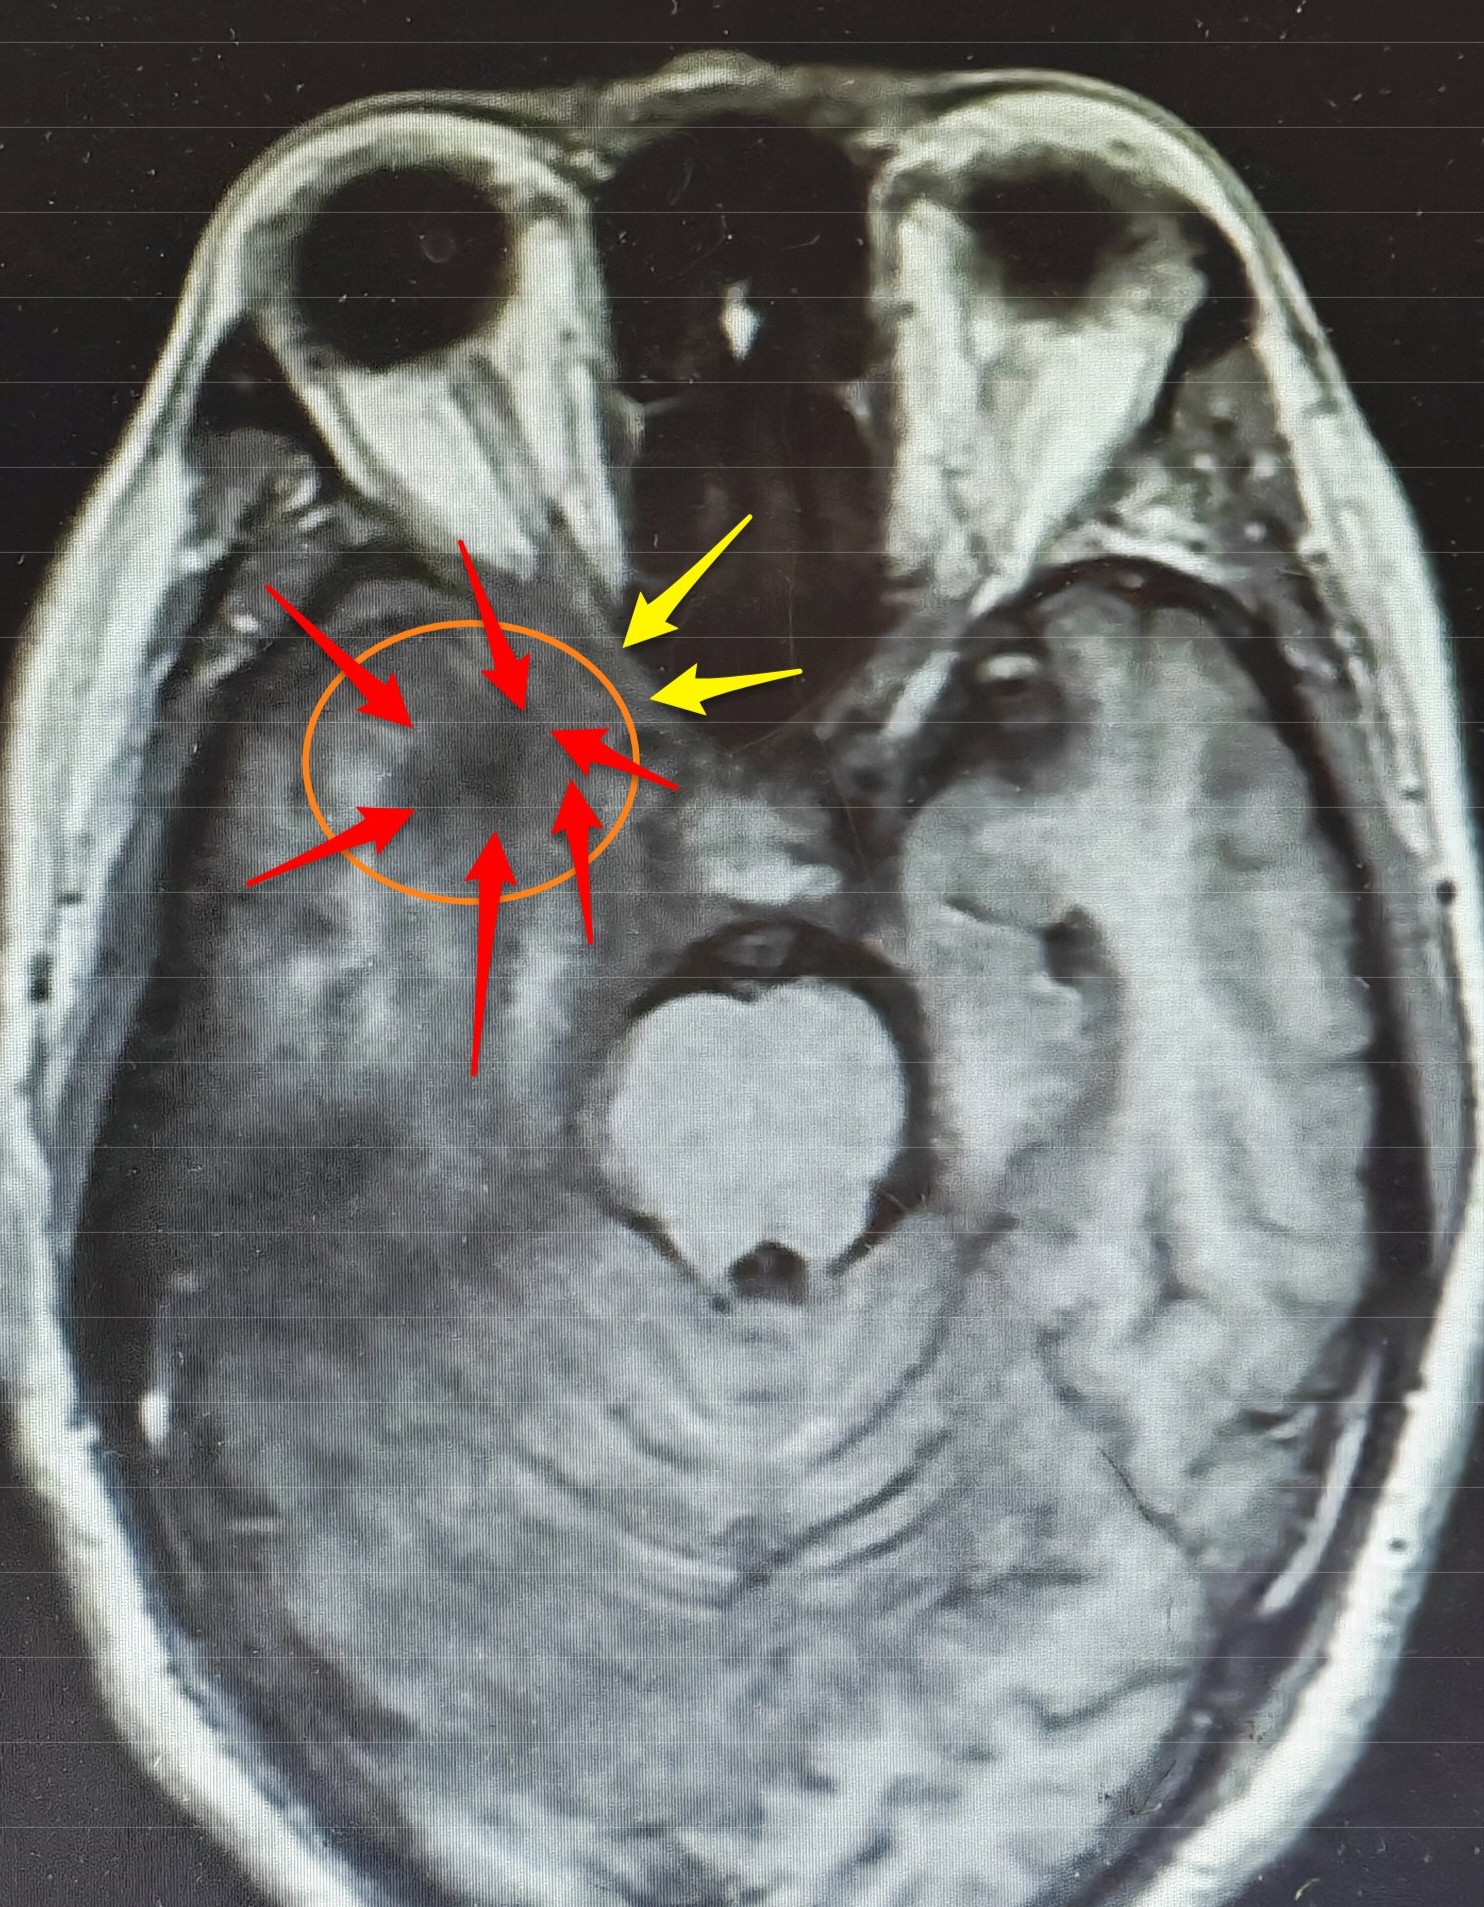

入院后,神经外科王典春主任为他完善了相关检查,对比院外之前的检查结果,发现他的右侧颞叶病变较前明显扩大,长径已达54毫米,且顶叶、枕叶发展,邻近脑膜增厚明显,“从影像学表现及实验室检查看,炎性病变可能性不大,再结合患者症状进行性加重的特点,胶质瘤也不能排除。”王典春主任在病例讨论中强调,右侧颞叶的占位性病变已压迫视神经,这正是导致李先生右眼失明的关键原因,若不及时干预,不仅视力恢复无望,病变还可能进一步侵犯脑组织,威胁生命安全。

虽然仍未完全明确病变性质,但神经外科专家团队一致认为,手术是当前最关键的治疗手段——通过手术切除部分颞叶病变组织进行术中冰冻及病理活检,可直接明确诊断,同时实施右侧视神经减压术,能缓解病变对神经的压迫,为视力恢复创造可能。

在麻醉团队的密切配合下,王典春主任凭借丰富的临床经验与精湛的操作技巧,小心翼翼地通过右侧翼点入路进入颅内,精准定位右侧颞叶病变区域,在保护周围正常脑组织与神经的前提下,成功切除部分病变组织送检,同时王主任还对受压的右侧视神经进行了细致减压,手术过程顺利。

最终术后病理报告也证实了李先生真正的病因是右侧颞顶枕叶的节细胞胶质瘤(WHO1级),这一结果为后续治疗提供了明确方向,神经外科专家团队将根据李先生手术后的恢复状况,联合肿瘤科等多个相关科室共同为他制定个性化的综合治疗方案,进一步控制病情发展。